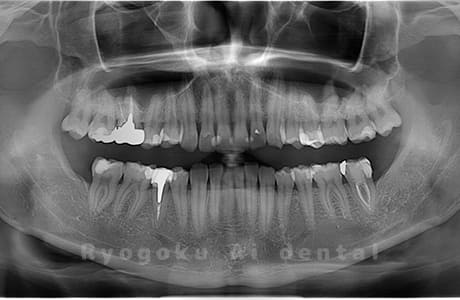

Case02

- 原因

- 下顎の水平埋伏智歯

- 治療内容

- 下顎の水平埋伏智歯を抜歯

<リスク・副作用>

手術後は痛み、腫れ、痺れなどの副作用が生じる場合があります。